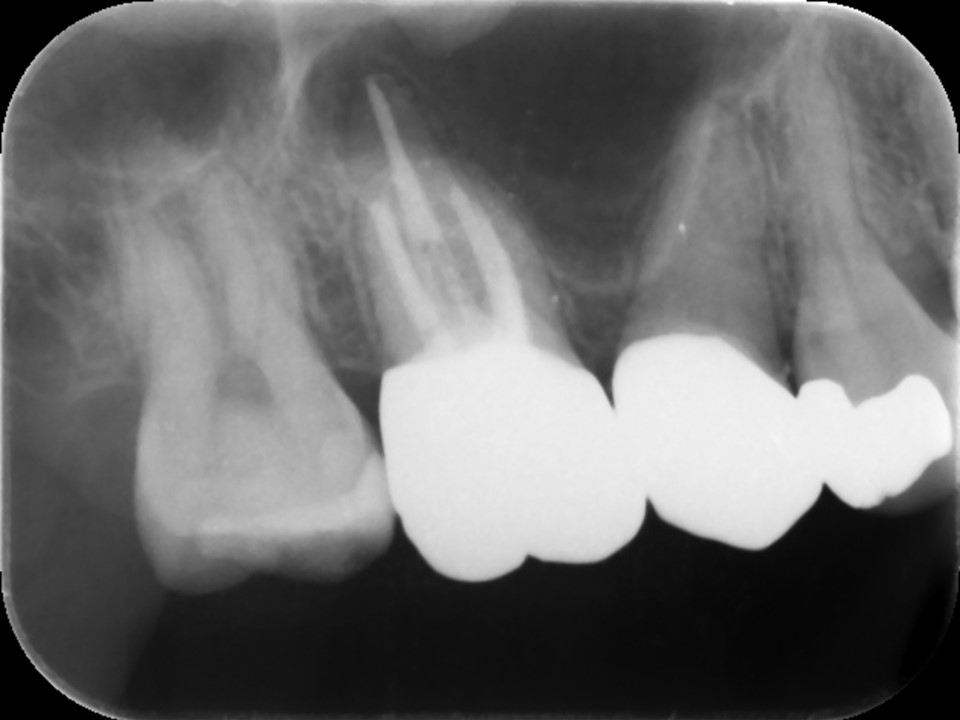

右側上顎第一大臼歯の初診時レントゲン。他院にて根管治療を行っているが良くならず、歯がひびく、黄色い鼻水が続いているとのこと。耳鼻科にて歯性上顎洞炎の診断を受ける。